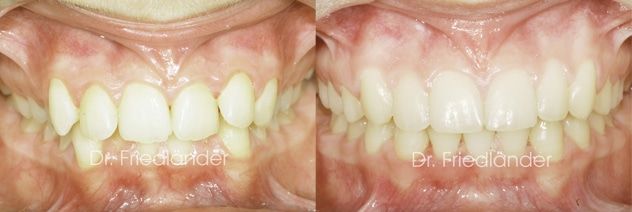

14 meses más tarde el tratamiento ya estaba terminado, se puede observar que conseguimos todos los objetivos propuestos; mejorar la salud de las encías, conseguir clase I en ambos lados y mejorar la mordida profunda.

En las siguientes fotografías se puede observar como ha mejorado la salud de las encías. Las raíces de los dientes inferiores ya no esta tan salidas fuera del hueso.